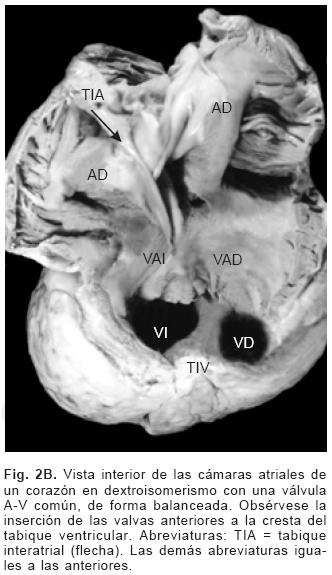

En los setenta corazones estudiados el situs atrial que predominó fue el solitus seguido de dextroisomerismo, inversus y levoisomerismo (Figs. 2A y 2B). La conexión A–V predominante fue concordante seguida de la doble entrada a ventrículo único, doble entrada a ventrículo derecho, ambigua y discordante (Tabla I). Los tipos de conexión ventriculoarterial se consignan en la Tabla II.

De los sesenta y cinco corazones con válvula común en veinticinco se determinaron los tipos de la clasificación de Rastelli que fueron los siguientes: en once (44%) las valvas anterosuperiores derecha e izquierda se insertaron a través de sus cuerdas tendinosas sobre la cresta del tabique ventricular y la CIV se ubicó en los espacios intercordales (tipo A de Rastelli) (Figs. 1A y 5A). En un espécimen las valvas anterosu–periores izquierda (valva puente) y derecha se insertaron sobre la cara derecha del tabique ventricular por debajo de su cresta (Fig. 5B) y en otro dicha inserción se hizo en la parte superior del cuerpo de la trabécula septomarginal (Fig. 5C). En ocho corazones (32%) la inserción de esas valvas se estableció en un músculo papilar situado en la unión del tabique ventricular con la pared libre del ventrículo derecho y la valva anterosuperior izquierda pasó como puente por encima de la CIV (tipo B de Rastelli) (Figs. 1B y 5D) y en seis corazones (24%) la inserción de las valvas anterosuperior izquierda (valva puente) y derecha se insertaron en un músculo papilar de la pared libre del ventrículo derecho y esta valva se ubicó por encima de la CIV (tipo C de Rastelli) (Figs. 1C y 5E). En los cuarenta corazones restantes no fue posible determinar los tipos de Rastelli debido a que treinta y tres de ellos presentaron doble entrada ventricular (Fig. 6A) dos tuvieron modificaciones anatómicas generadas por la cirugía y cinco por presentar mutilaciones realizadas durante la necropsia. Los cinco especímenes con dos válvulas separadas tuvieron estructura trifoliada dentro de la unión A–V común (Figs. 3B y 6B); la válvula A–V izquierda mostró una valva lateral y dos septales anterior y posterior unidas a la cresta del tabique ventricular, lo que obliteró la CIV (Fig. 6C). La válvula A–V derecha mostró una valva septal displásica, una anterior y una posterior (Figs. 3B y 6B).

El DSA–V puede presentarse en cualquier situs lo que es más frecuente dentro de la población con dextroisomerismo en la que los corazones muestran múltiple asociación de defectos intracardíacos. Otras cardiopatías congénitas asociadas son la estenosis pulmonar, doble salida de ventrículo derecho, Tetralogía de Fallot, transposición de las grandes arterias, doble entrada ventricular.